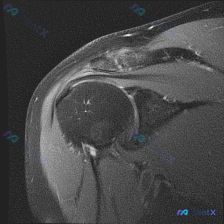

看到一份肩部MRI的病例资料,用户提到观察到"盂唇病变",但影像报告显示冈上肌腱全层撕裂伴滑囊积液,关节软骨与盂唇尚完整。大家觉得这个病例更倾向于什么诊断?是单纯的肩袖撕裂,还是合并盂唇病变?欢迎讨论。

整理了一份肩部MRI病例讨论材料,医生的核心问题是排查盂唇病变,但看影像发现了一些矛盾点。先放MRI T2序列冠状位的分析: 1. 骨性结构:肱骨头、肩峰及锁骨远端轮廓尚可,未见骨折线或骨髓水肿 2. 肌腱与肩袖:冈上肌腱在肱骨大结节止点处形态异常,连续性中断,T2高信号 3. 关节与滑囊:肩峰下-...

最近整理了一份肩部MRI的病例讨论材料,患者主要问题是肩部疼痛,但问题明确指向"盂唇病变"范畴。先看T2冠状位图像的关键发现: 1. 冈上肌腱在肱骨大结节止点处有显著高信号,连续性可能中断 2. 肩峰下-三角肌下滑囊有明显的高信号积液 3. 关节盂唇区域信号存在改变 大家觉得这个病例更符合哪种诊断?...

看到一个肩部MRI(冠状位)的病例资料,用户最初的问题是关于「盂唇病理」,但整理的分析报告里有几个点挺值得讨论的: 先放影像的关键发现: - 冈上肌腱连续性中断,断端回缩,伴冈上肌肌腹萎缩、脂肪浸润 - 肩峰下-三角肌下滑囊积液,肩峰下间隙变窄,肱骨头上移 - 肱骨头大结节下方骨髓水肿 - 盂唇形态...